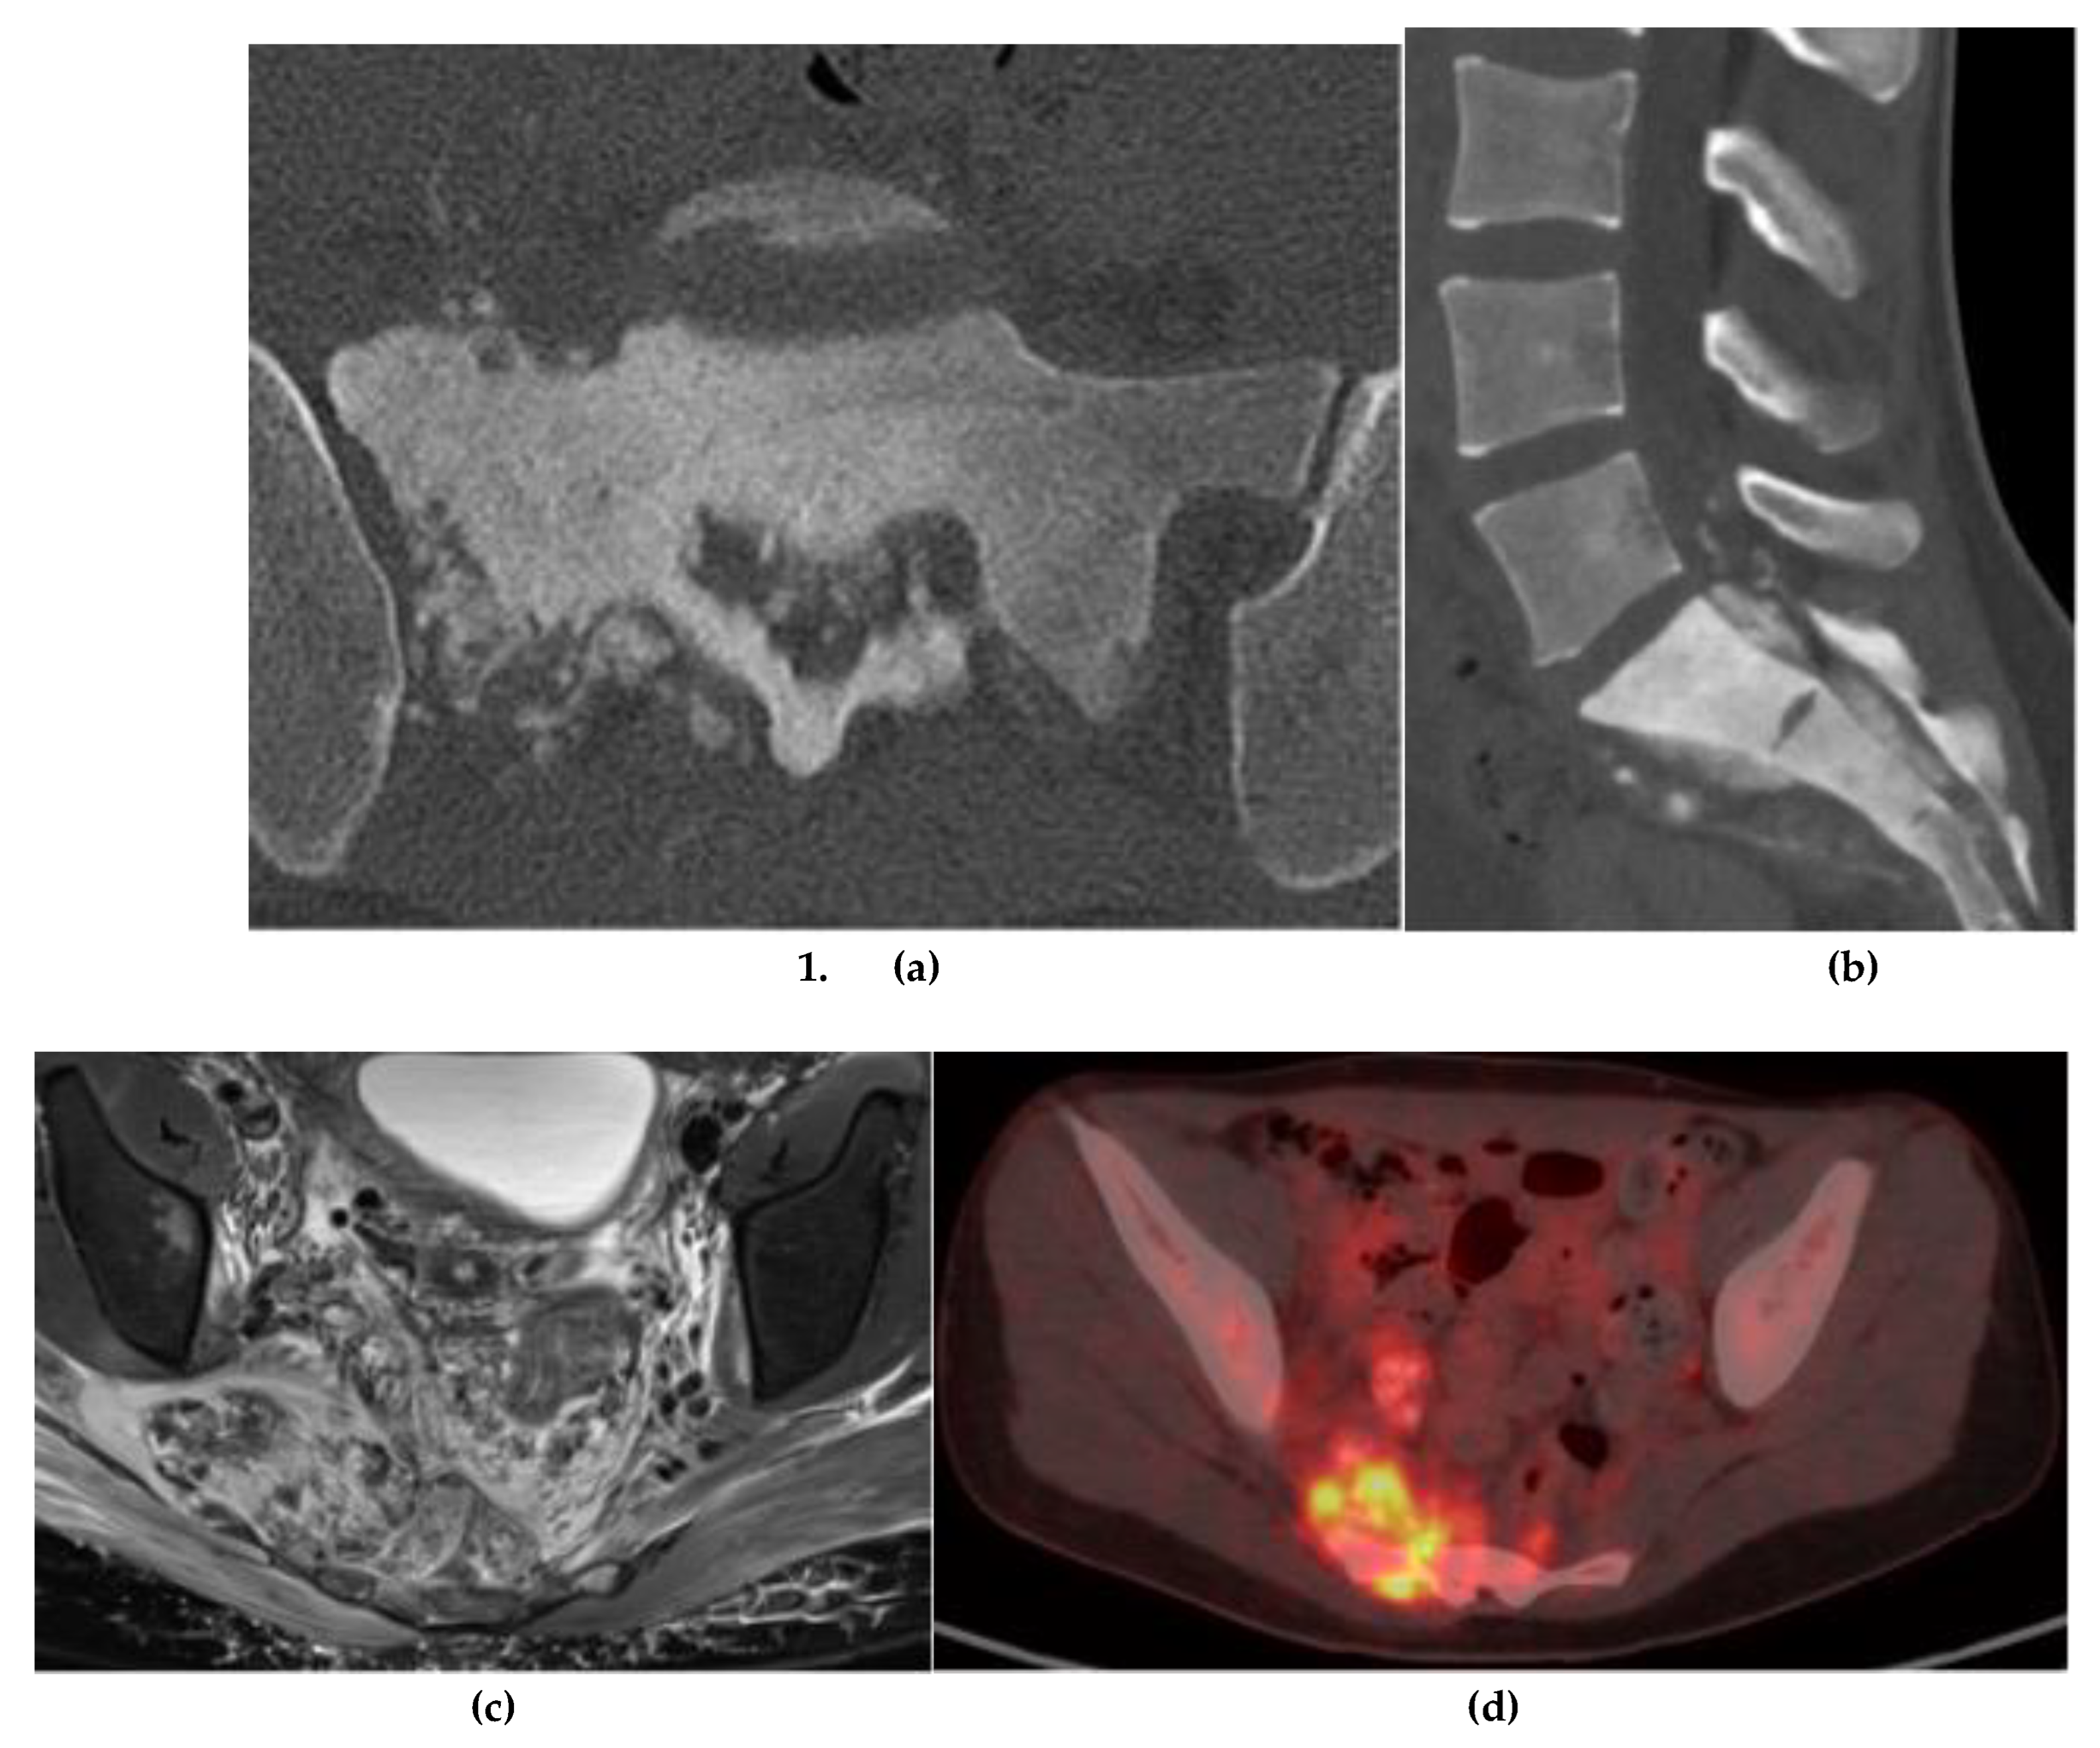

Chondrosarcoma

3. Notochordal

Chordoma